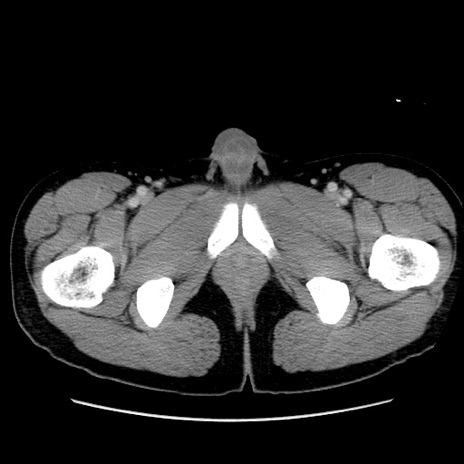

症例36(横断像)

【症例】20歳代 男性

【主訴】心窩部痛

【現病歴】今朝より上腹部痛あり。一旦軽快していたが再度出現したため救急要請。昨日夕に白身の魚を含む刺身を食べた。

【身体所見】BP 136/89mmHg、HR 74/min、BT 37.0℃、腹部:膨満、軟、心窩部に圧痛あり。反跳痛なし、筋性防御なし、腸雑音やや亢進あり。

【データ】WBC 17700、CRP 0.48